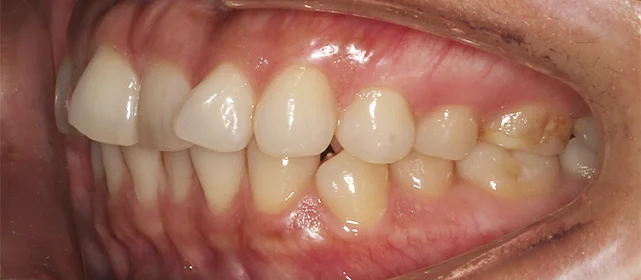

Нарушение соотношения челюстей и неправильное положение зубов — зубные ряды смыкались некорректно, зубы стояли со смещением.

Проблема: В клинику обратилась пациентка — беспокоили неровные зубы и неправильное смыкание. Зубные ряды сходились некорректно, зубы стояли со смещением, что влияло и на внешний вид, и на распределение нагрузки при жевании.

Решение: Поставили элайнеры 3D Smile на обе челюсти. Лечение заняло 4 года и потребовало нескольких последовательных этапов коррекции. Капы менялись каждые 1–2 недели, на контрольных визитах отслеживали прогресс и выдавали новые наборы. Зубы встали в правильное положение, смыкание нормализовалось. Зафиксировали ретейнеры на обе челюсти, изготовили ретенционные капы. Пациентка прошла онлайн-консультацию с ортопедом для оценки дальнейших шагов.